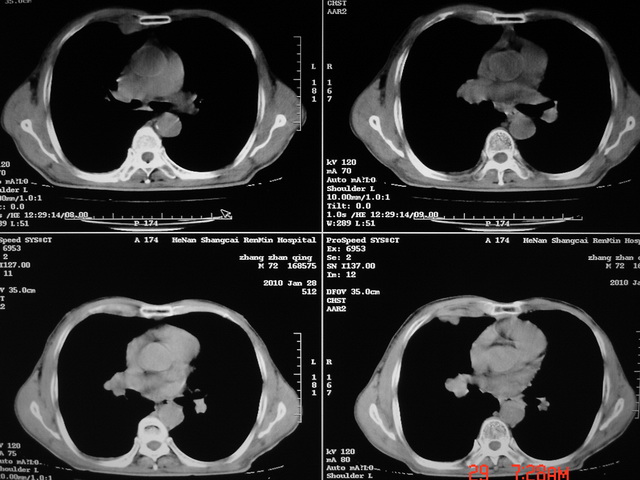

标题: CT24386:M 72岁农民 右侧胸痛6月余,咳嗽,无发热、咯血等 [打印本页]

xx m 72岁农民 右侧胸痛6月余,咳嗽,无发热、咯血等

右下周围型肺癌,并右肺门、纵膈淋巴结、内乳淋巴结转移,右胸膜转移累及前胸壁。鉴别:脓肿、tb、淋巴瘤。病理类型可能为大细胞型。

这个病人有点复杂了,上纵隔像是占位,右肺下叶见壁光整厚壁空洞加液平,像是肺脓肿,中叶病灶牵涉到胸膜及胸壁,形态看像是炎性病变,总之不能除外恶性病变,还是穿刺或增强后再说。

右下周围型肺癌。偏心空洞形成伴感染。

右下周围型肺癌伴转移

支持2搂,考虑右肺下叶周围性肺癌伴肺门及纵膈淋巴结转移!右侧前纵膈病灶,还是一元论考虑为胸壁或胸膜转移瘤。

支持 右肺下叶周围型肺癌并右肺门、纵膈淋巴结、内乳淋巴结转移,右胸膜转移累及前胸壁。